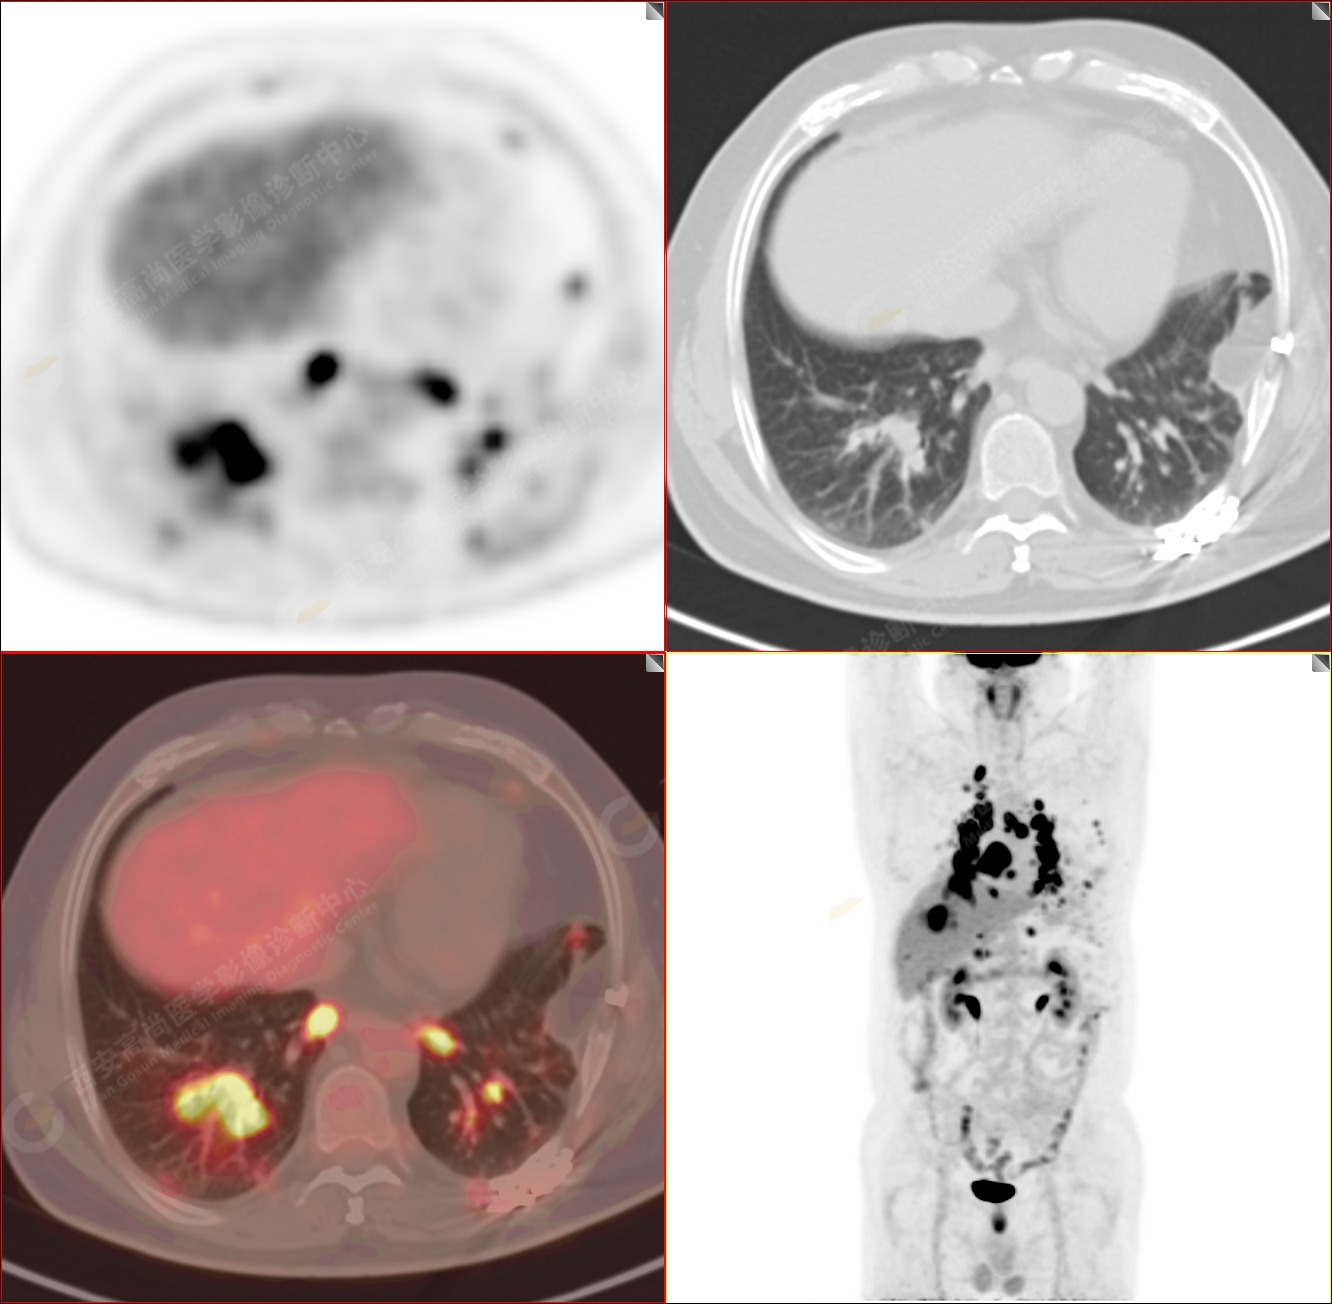

PET-MR圖像